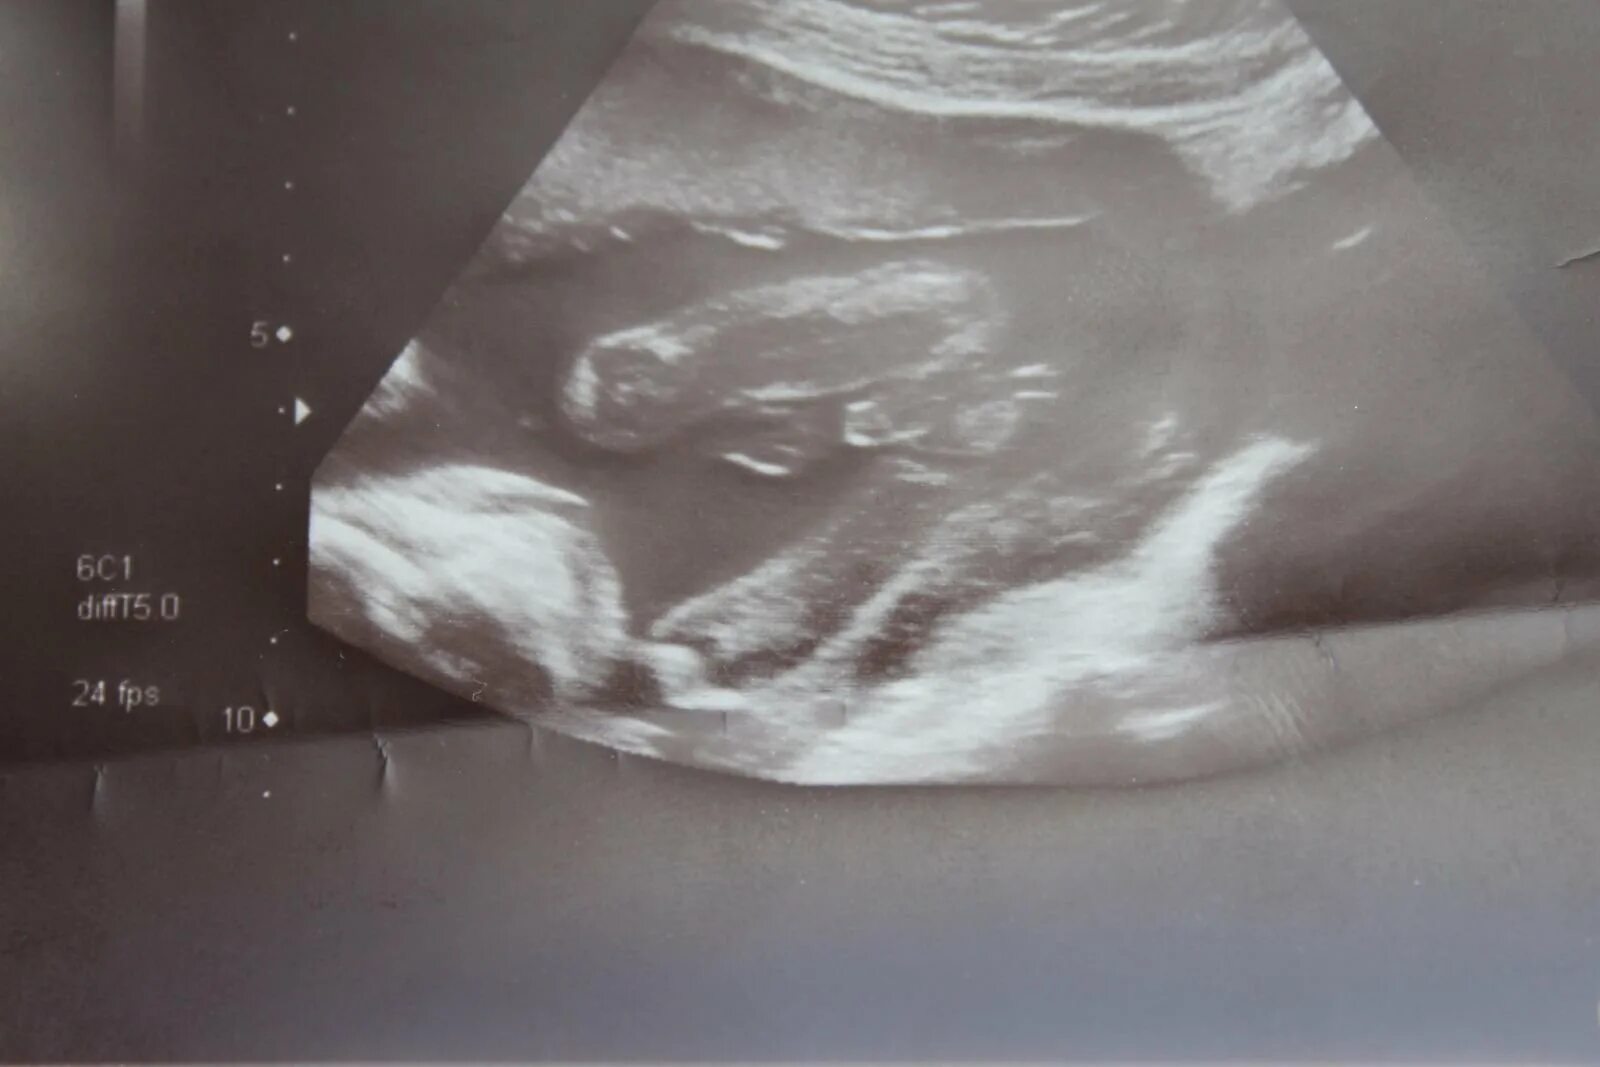

Через 20 недель